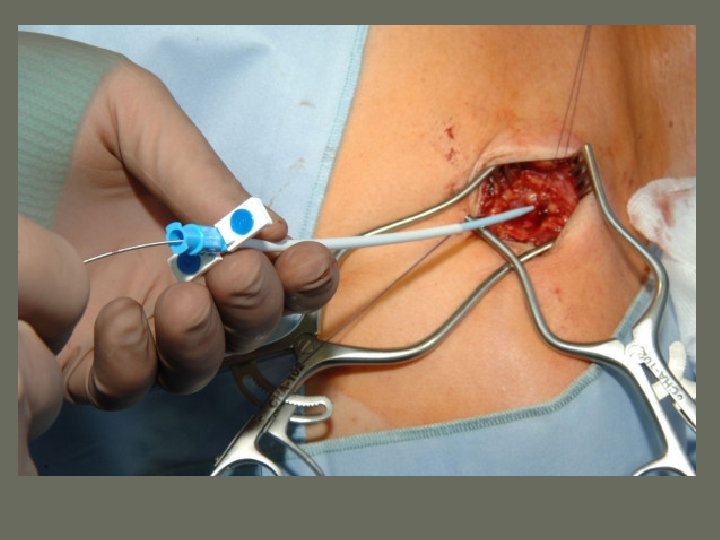

General Angiography • Injection Methods 1. Direct Injection – Direct stick into the _______ under examination 2. Percutaneous Catheterization – Seldinger technique – allows for the introduction of a needle, guide wire, and ______ into a specific vessel